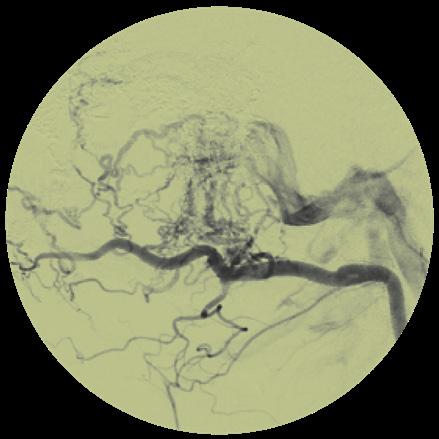

A new study has found that nearly one in 10 hepatocellular carcinoma (HCC) lesions were not detected on cross-sectional imaging using computed tomography (CT) or magnetic resonance imaging (MRI) when compared to lipiodol staining. Presenting these new data at the Society of Interventional Oncology (SIO) annual meeting (4–8 February, Savannah, USA), Emilio Cavazos-Escobar (University of Texas Health San Antonio, San Antonio, USA) emphasised that, although a “diagnostic discrepancy” does exist, the positive predictive value of cross-sectional imaging remained high, meaning lesions are more often than not correctly identified as HCC.

THE MOTIVATION FOR THEIR investigation arose after CavazosEscobar and colleagues began noticing unexpected lesions appearing on routine ‘stain-and-ablate’ procedures, he noted.

“Typically, the patient will receive cross-sectional imaging—either four-phase or three-phase CT or MRI with or without contrast. Then, if the intention is to treat the lesion, we schedule a clinic appointment where a targeted ultrasound is performed,” Cavazos-Escobar detailed. He

continued that, in some cases, if the lesion is not apparent on ultrasound or is poorly conspicuous on noncontrast CT, they schedule the patient for a stain-and-ablate procedure to better delineate the lesion’s position and assess adjacent anatomical structures that may be involved.

To compare the diagnostic performance of cross-sectional imaging versus lipiodol staining, Cavazos-Escobar et al performed a retrospective review of 181 patients who underwent stain-and-ablate

procedures between August 2020 and September 2025. Within the cohort of 181 patients, 282 lesions were identified by lipiodol staining. Out of the total of 282, 246 lesions were correctly detected and classified as LR-5—using the Liver Imaging Reporting and Data System (LIRADS)—via crosssectional imaging, for an overall sensitivity of 87.2%.

“Interestingly, 27 (9.6%) lesions were not detected altogether on cross-sectional imaging, and thirteen lesions were misclassified as false positives”, Cavazos-Escobar explained. “This meant that these were labelled

LR-5, but when the patient was taken for lipiodol staining, there was no enhancement of the supposed tumor and therefore these were classified as not true lesions”. Additionally, nine lesions were misclassified as false negatives and were either classified as LR-3 or lower which eventually did stain with lipiodol.

Speaking at this year’s SIO annual meeting, Cavazos-Escobar relayed that the positive predictive value for cross-sectional imaging was 95%. “This means that when CT or MRI detects a lesion, there’s a good likelihood that it will be correctly identified as HCC,” he stated.

It’s not uncommon to see patients whom we initially thought only had one lesion, inject lipiodol, and then all of a sudden, the patient has three lesions.”

“It’s not uncommon to see patients whom we initially thought only had one lesion, inject lipiodol, and then all of a sudden, the patient has three lesions. We wanted to further investigate that discrepancy at our institution. There are some data available, but they’re very scarce, and there isn’t much research involving the use of lipiodol, so we’re hoping the present analysis meaningfully adds to the literature.”

Summarising, Cavazos-Escobar stated that a “diagnostic discrepancy does exist, which suggests that CT or MRI may underestimate tumour burden in some patients”.